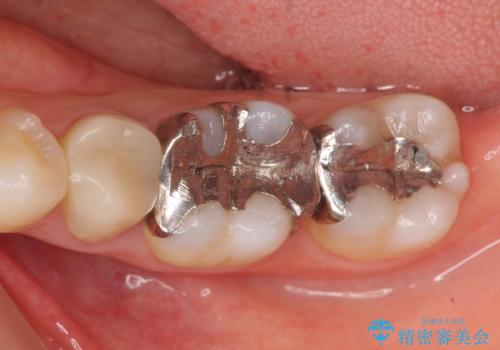

- 左下奥歯の銀歯が気になると来院された方の症例です。

左下7はセラミックインレーによる修復を行い、左下5、6はオールセラミッククラウンによる補綴を行いました。